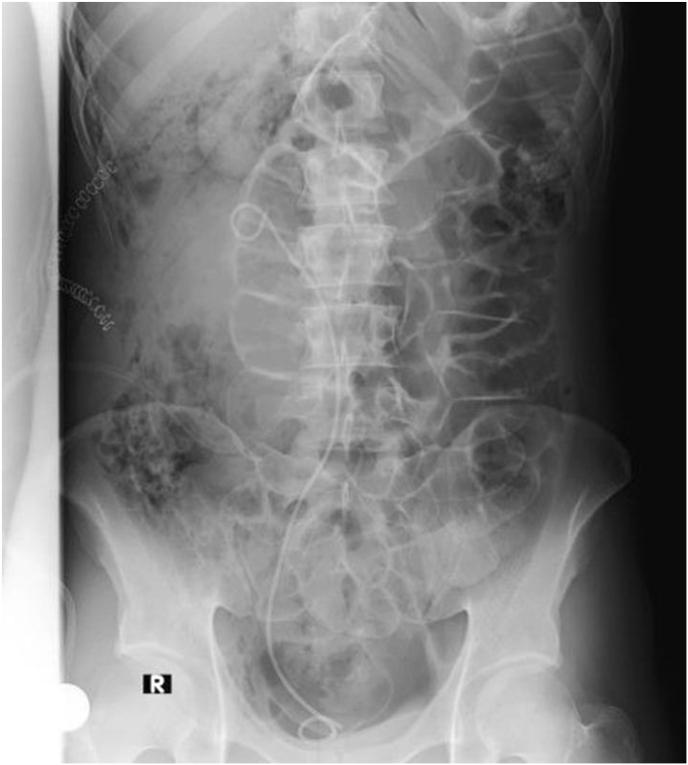

A 22-year-old male smoker presented with intermittent right flank pain lasting over a year. He had a history of atrophied left kidney and gout. Physical exam revealed mild right renal angle tenderness.

Initial imaging, pointed to a diagnosis of ureteropelvic junction stenosis. During surgery, a type two retrocaval ureter was discovered. Transposition pyelo-pyelostomy was performed to repair the ureter, and a double-J stent was inserted.

一名22岁男性吸烟者,间歇性右侧腰痛持续一年多。他有左肾萎缩和痛风病史。体格检查发现右侧肾角轻度压痛。

初步影像学检查提示输尿管肾盂连接处狭窄的诊断。手术中发现了二型腔后输尿管。进行了肾盂-肾盂吻合术修复输尿管,并插入了双J支架。